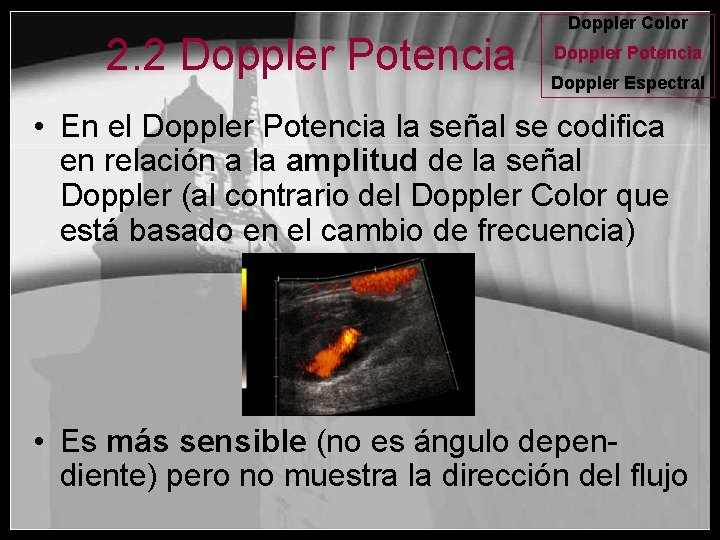

2. 2 Doppler Potencia Doppler Color Doppler Potencia Doppler Espectral • En el Doppler Potencia la señal se codifica en relación a la amplitud de la señal Doppler (al contrario del Doppler Color que está basado en el cambio de frecuencia) • Es más sensible (no es ángulo dependiente) pero no muestra la dirección del flujo